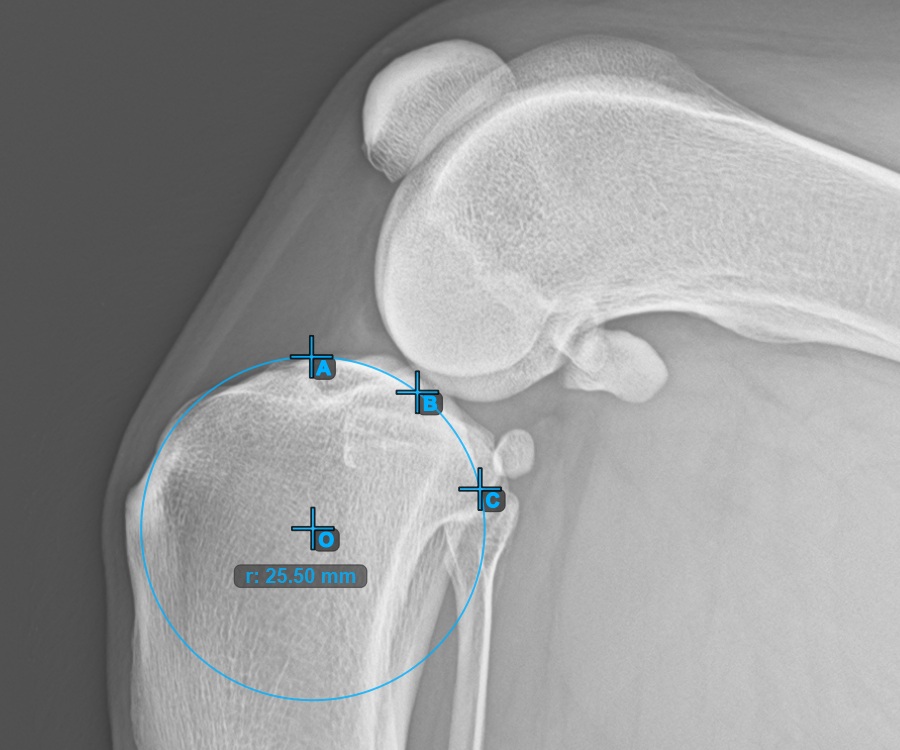

To complete the TTA - 1 Condylus variant of TTA measurement procedure mark the most dorsal point of the Crista Tibiae (Tuberositas Tibiae). The distance between the Tuberositas Tibiae and the line passing along the most cranial point of the Patella is the required adjustment for the TTA procedure.

The image below depicts the usual placement of the tibial tuberosity, the most prominent point of the tibial crest.

Modify the points constructing the measurement to recalculate the required advancement that should be made during the TTA procedure.